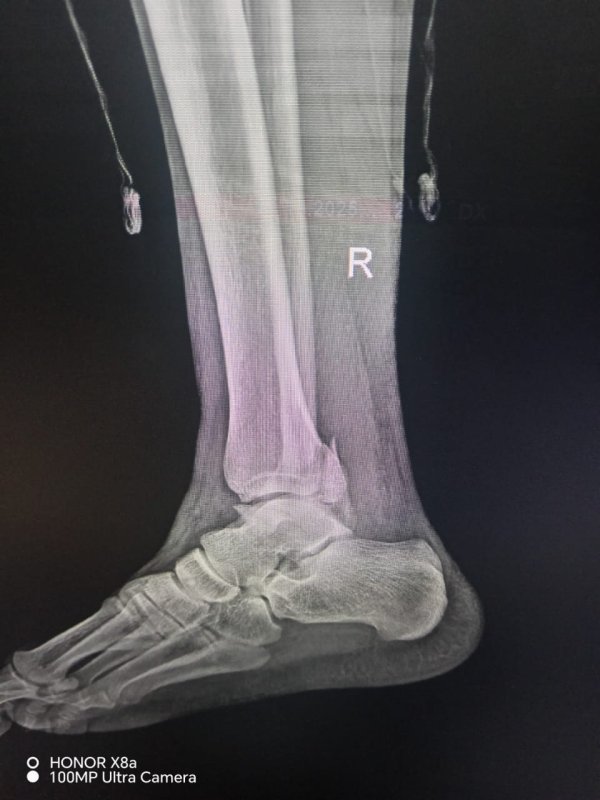

Rentgen müayinəsindən sonra vətəndaşa ayağında üç yerdən sınıq və ya qırıq olduğu bildirilərək mil (metall konstruksiya) taxılması məqsədilə əməliyyata cəlb olunub.

Məlumat üçün qeyd edək ki, vətəndaşın rentgen görüntüləri də redaksiyamıza təqdim olunub.